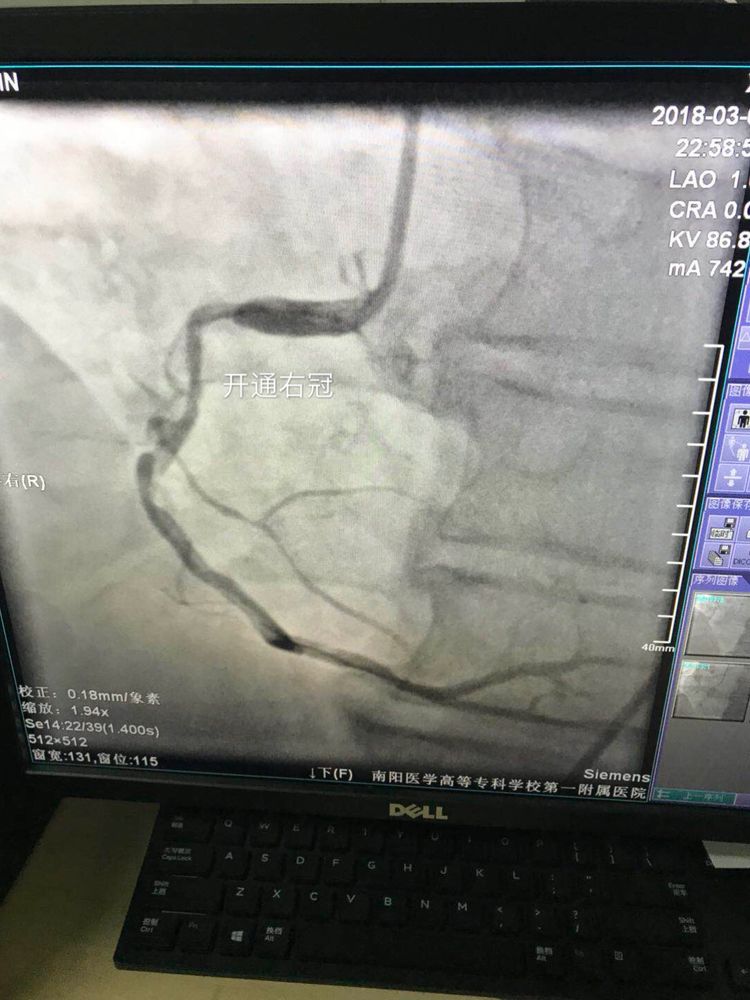

经过一个多小时的努力,开通右冠状动脉,血流恢复。血管一开通了,病人心率逐渐开始恢复。由室性心动过速转变为房颤。